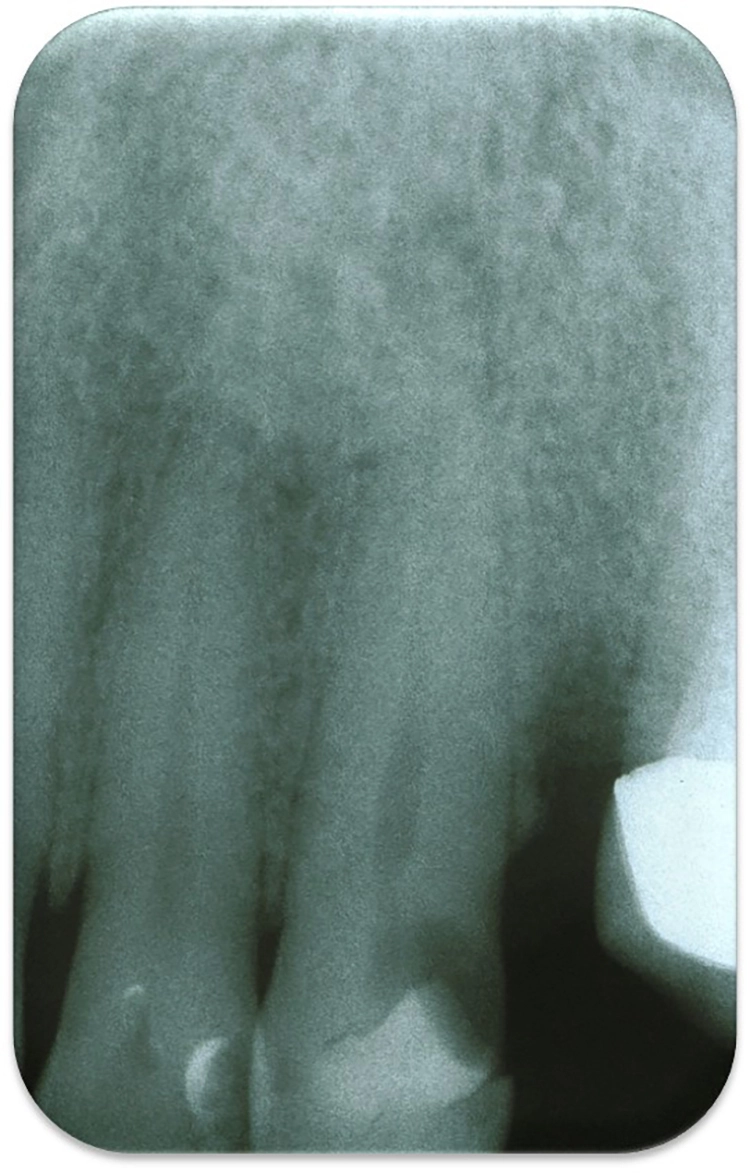

Röntgendiagnostik

Eine oder bei Bedarf auch mehrere neue Einzelzahnaufnahmen mit unterschiedlichen Projektionen mit vollständiger und deutlicher Darstellung der Periapikalregion sind zur Diagnostik unverzichtbar. Es findet sich meistens eine apikale Läsion, deren Größe aber sehr unterschiedlich ausfallen kann, abhängig von der Geschwindigkeit, mit der sich der Abszess entwickelt hat [9] (Abb. 3 und 4).

Im DVT ist ein Abszess früher zu erkennen als in der Einzelzahnaufnahme, in der er erst nach Erreichen der Kompakta dargestellt wird [12]. Zur Abszessdiagnostik ist eine DVT allerdings nicht unbedingt notwendig, da die klinischen Symptome und Befunde in der Regel ausreichend sind.